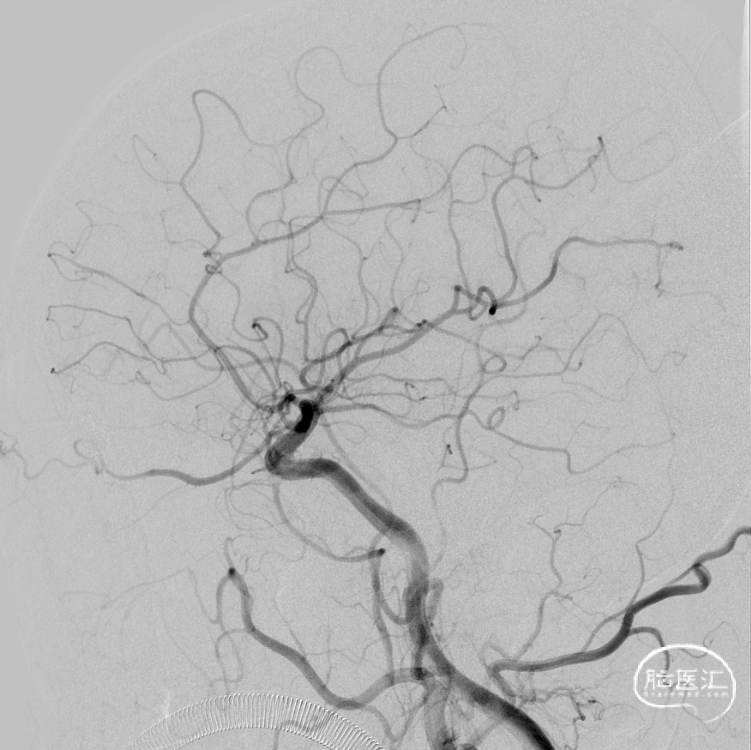

二期治疗

治疗经过